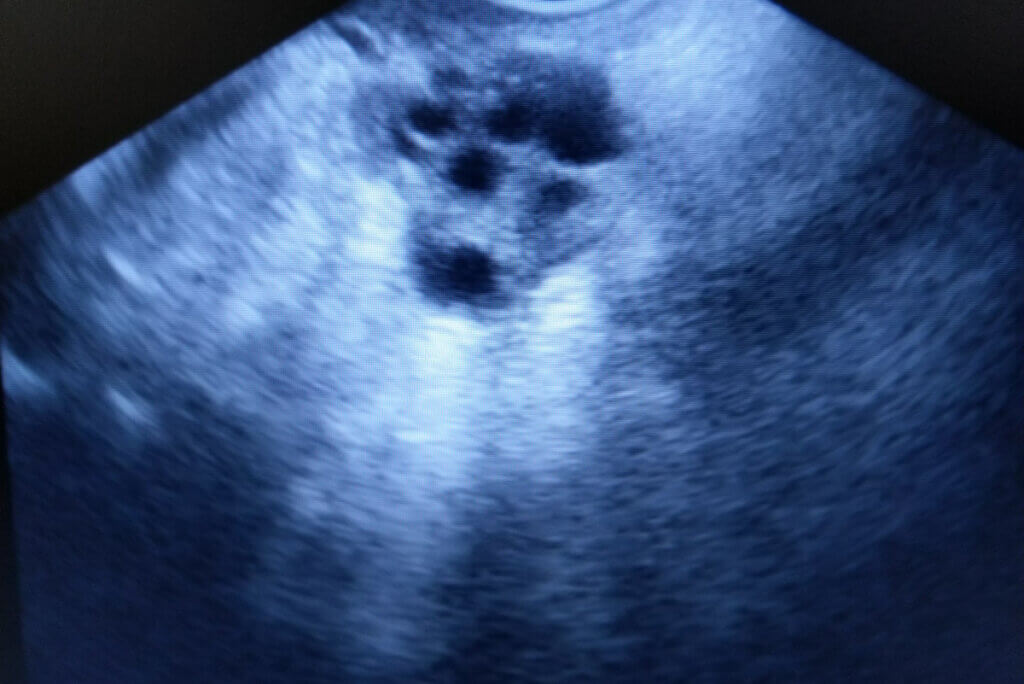

Esta es una alteración endocrina caracterizada por presentar signos de exceso de andrógenos, obesidad leve y ciclos menstruales irregulares o ausentes. Además, también existen diversos cambios en los ovarios, los que tendrán múltiples quistes foliculares de 2 a 6 milímetros de diámetro.

En ocasiones, en vez de formarse un óvulo maduro, el desequilibrio hormonal causará la formación de quistes ováricos, los que son pequeñas bolsas rellenas de líquido. A pesar de ser una enfermedad descubierta hace muchos años, los médicos aún desconocen la causa precisa de la misma.

Además, es posible que se realice un examen físico genital en busca de tumoraciones o bultos. Por último, una ecografía abdominal observará ovarios aumentados de tamaño y con múltiples quistes.